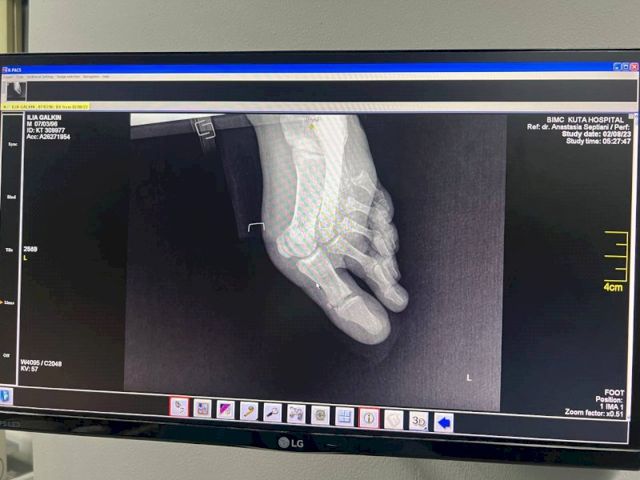

По его словам, сразу после аварии друзья ведущего повезли его в частную больницу. Однако цены там были «сумасшедшие». Тогда Илью отвезли в госпиталь BIMC Kuta. На первичном осмотре выяснилось, что у него множественные переломы и открытый перелом бедренной кости, разорваны мышцы и связки, требуются серьезные операции.

«Первую операцию сделали сегодня, он сейчас в реанимации. Говорят, что состояние стабильное. Операция и нахождение в больнице стоят около 30-50 тыс. долларов. Для нашей семьи это большие деньги, поэтому друзья открыли сбор на лечение. Но волнует и вопрос реабилитации. Либо Илья будет проходить ее там, а это очень дорого, либо его как-то надо транспортировать в Россию», - говорит Павел Галкин.